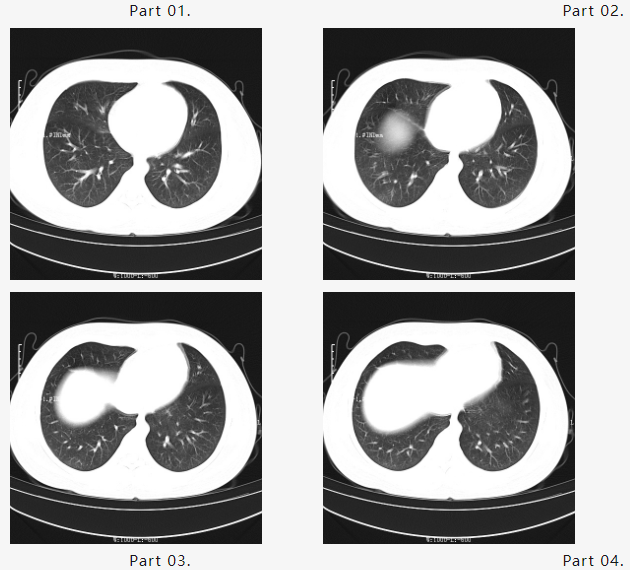

为进一步观察病情变化,马博建议小毛母亲继续住院行巩固支持治疗,终于,在大家共同努力下迎来了出院前最后一次复查胸部CT,结果如下:

一段时间后,小毛“白肺”已经消退,肺呼吸功能完全恢复,取得非常满意的治疗效果,随即出院。